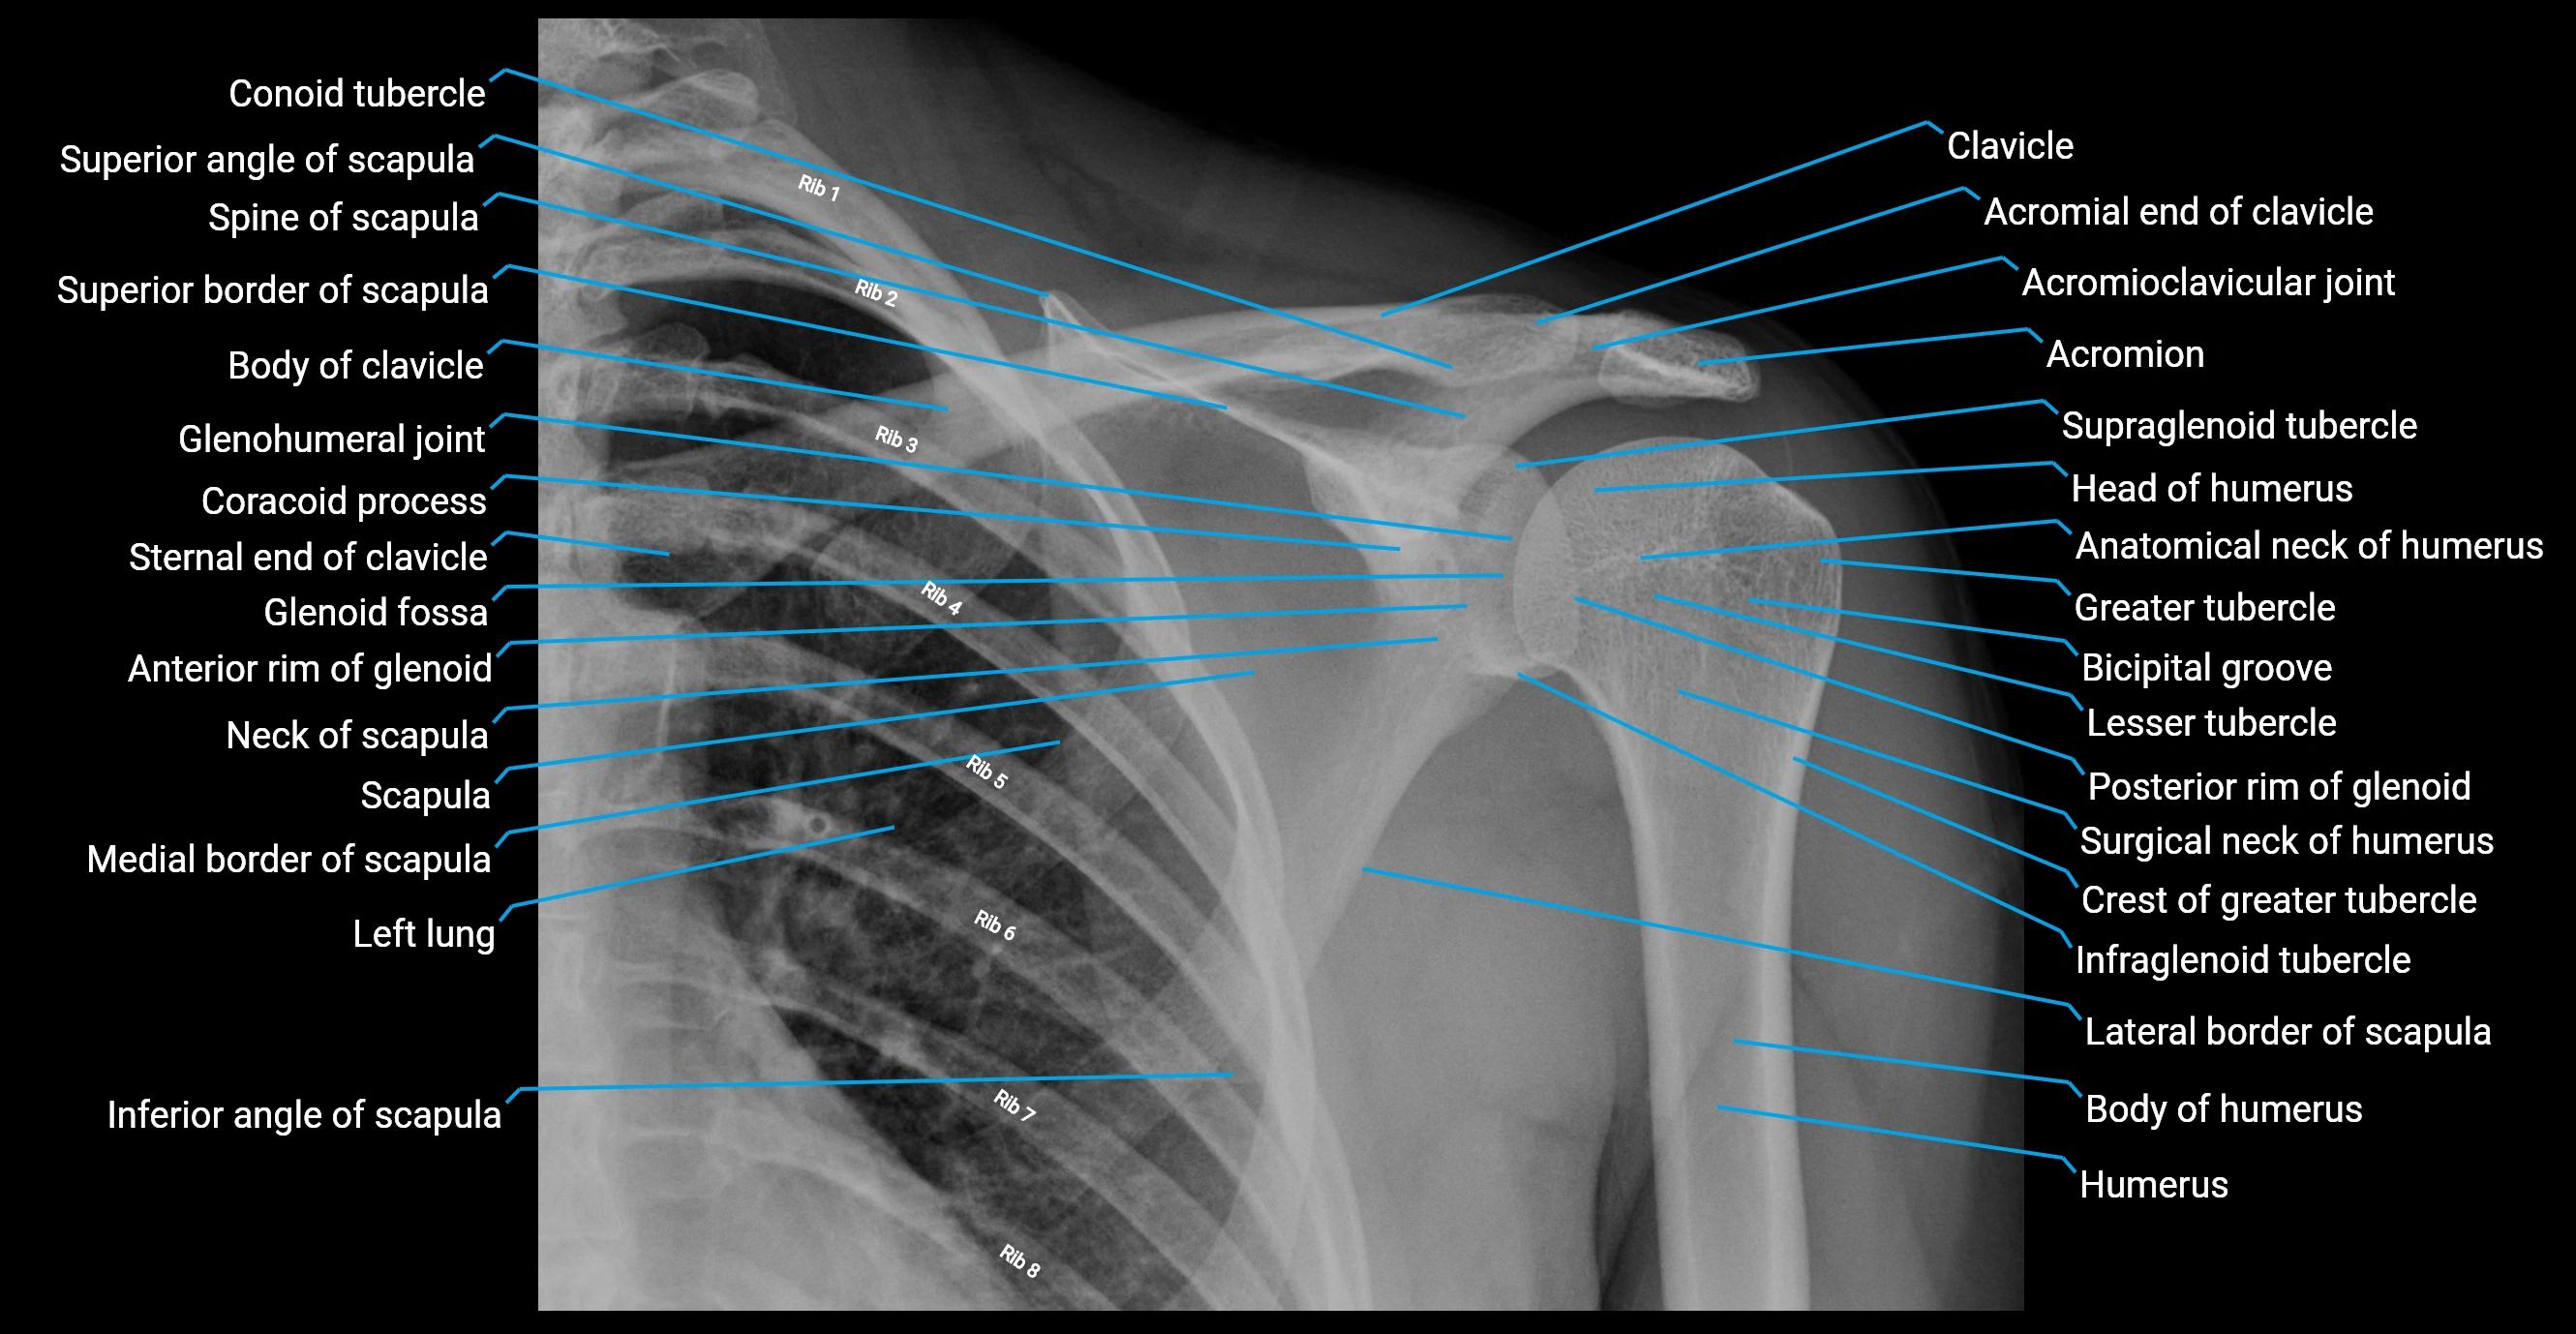

The acromial end of the clavicle is the flattened lateral extremity of the clavicle that articulates with the acromion of the scapula to form the acromioclavicular (AC) joint. Unlike the sternal end, the acromial end is broad and compressed. Its articular surface is oval, directed downward and medially, and covered with fibrocartilage.

The AC joint is stabilized by the acromioclavicular ligaments (superior and inferior) and reinforced by the coracoclavicular ligaments (conoid and trapezoid), which prevent vertical displacement. Small intra-articular fibrocartilaginous discs may be present.

This region is highly mobile, allowing scapular rotation, gliding, and elevation, which are essential for full shoulder motion. It is clinically significant as a frequent site of degeneration, separation injuries, fractures, and osteoarthritis.